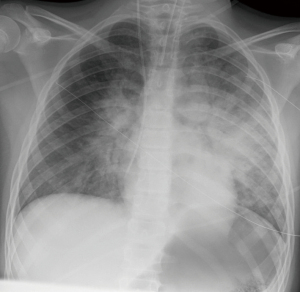

| Chest X-ray | Pulmonary oedema |

On admission, the patient was hypotensive despite high doses of catecholamines. Initial ECG showed tachycardic sinus rhythm (140 bpm) with ST-depressions in II, III, augmented voltage foot (aVF) and elevations in V1–4 (see Figure 2), chest X-ray revealed pulmonary oedema (see Figure 3). Blood gases showed lactate acidosis (lactate max. 8 mmol/L, pH min. 7.22) and cardiac enzymes were highly increased (see Figure 2).